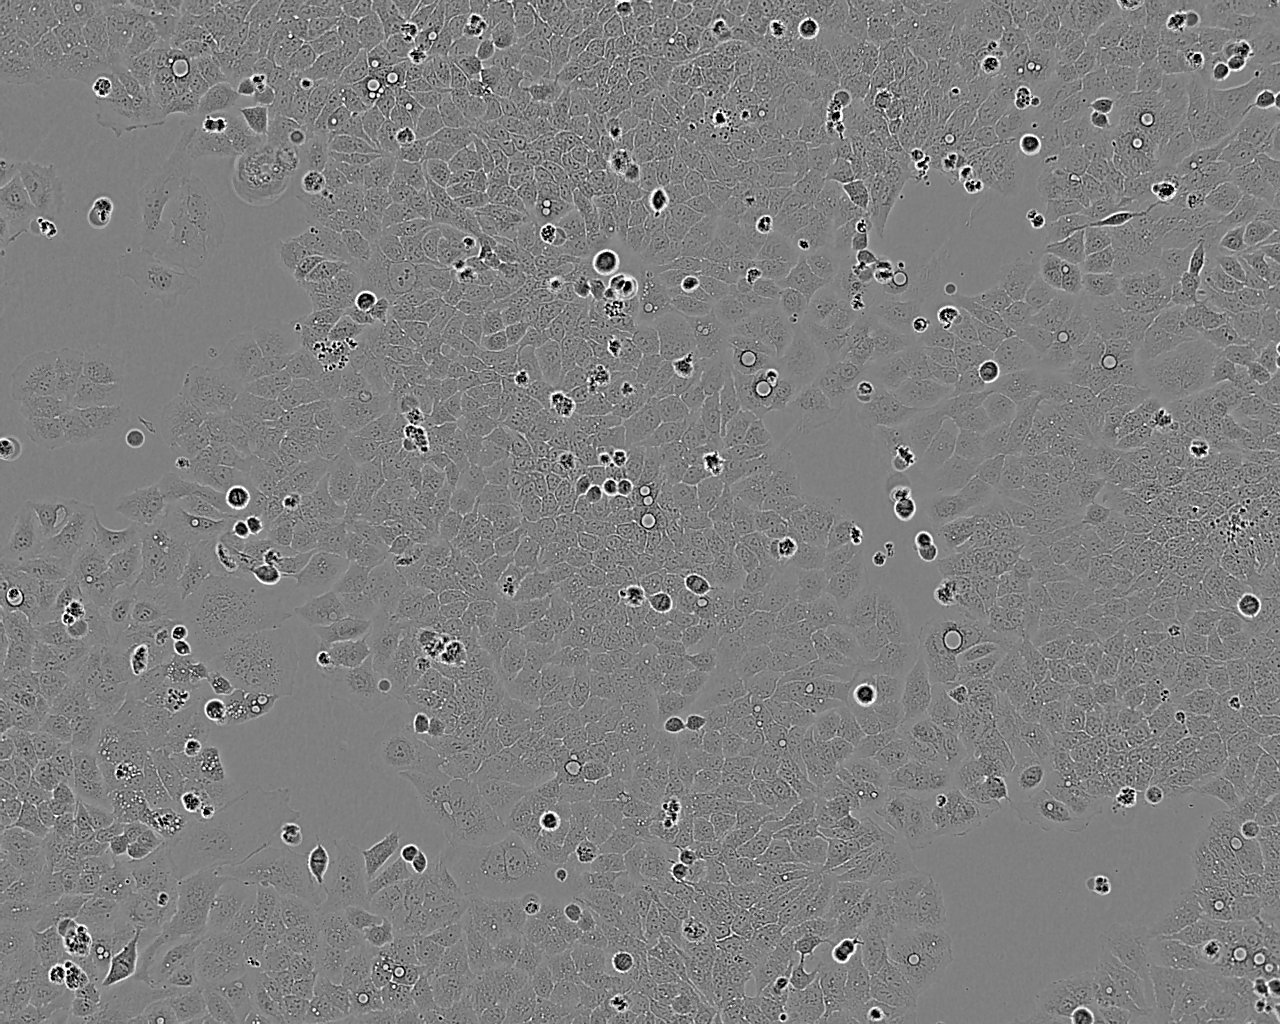

细胞背景资料:该细胞是1955年由PuckTT,MarcusPI和CieciuraSJ建系的,含HPV-18序列;角蛋白阳性;可用于与染色体突变、细胞营养、集落形成相关的哺乳动物细胞的克隆分析。

细胞形态:上皮细胞样

细胞生长:贴壁

细胞生长特性:贴壁生长

细胞形态特性:上皮样